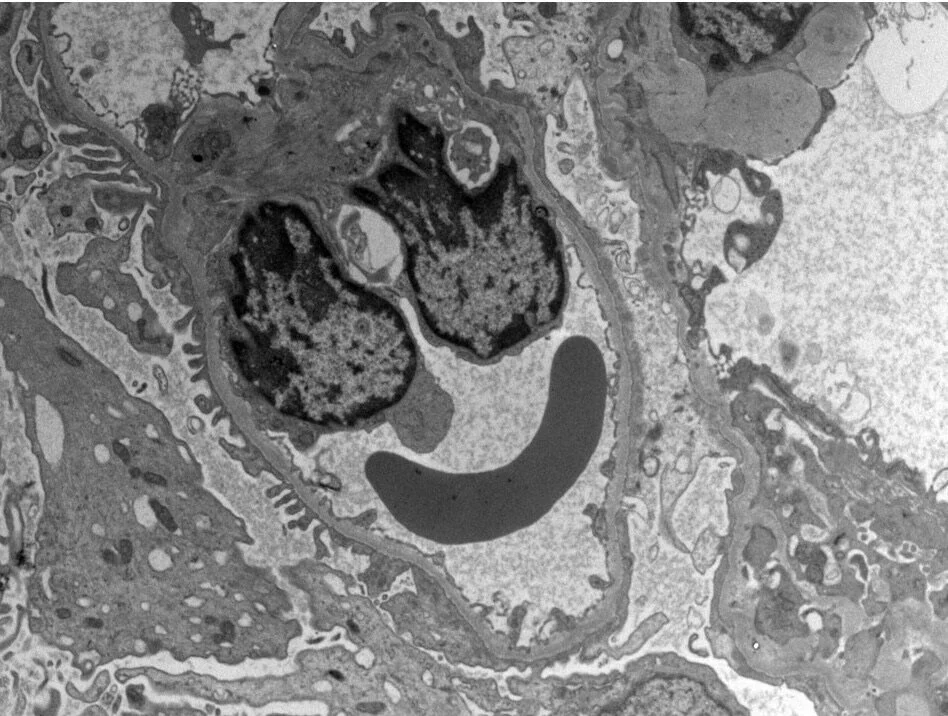

Ocular pathology is a broad discipline that not only involves diagnostic or post-mortem evaluations; Ocular histology is more frequently requested during in vivo preclinical testing as a method of predicting potential clinical adversities. Within a translational good laboratory practice (GLP) environment, it remains crucial that the pathologist not only feels comfortable to diagnose the ocular lesion but also be able to locate each one of them. Best practices recommend that the pathologist must have access to the standard operating procedures (SOPs) from each step in the study design. This involves the route of exposure, clinical ophthalmic findings, necropsy observations, and histology procedures. Ocular treatment-related findings need to be differentiated from common artifacts, spontaneous changes, and iatrogenic findings, so histology sections of good quality with proper orientation and minimal tissue artifacts are essential.

4. Know your Anatomy: Eyes do show anatomic specificities depending on the laboratory animal species. Therefore, awareness about these macroscopic and microscopic anatomic specificities will help you to achieve your histology targets.

b. As a microscopic example: human primates are the only laboratory animal species to possess a fovea which is the equivalent of the fovea centralis in humans. The fovea is responsible for the sharp central visions also called foveal vision. Therefore, it’s often mandatory to have the fovea present at least in one of the slides for further histopathological evaluations. Advanced skills are needed during the cutting stage in order to locate the fovea.